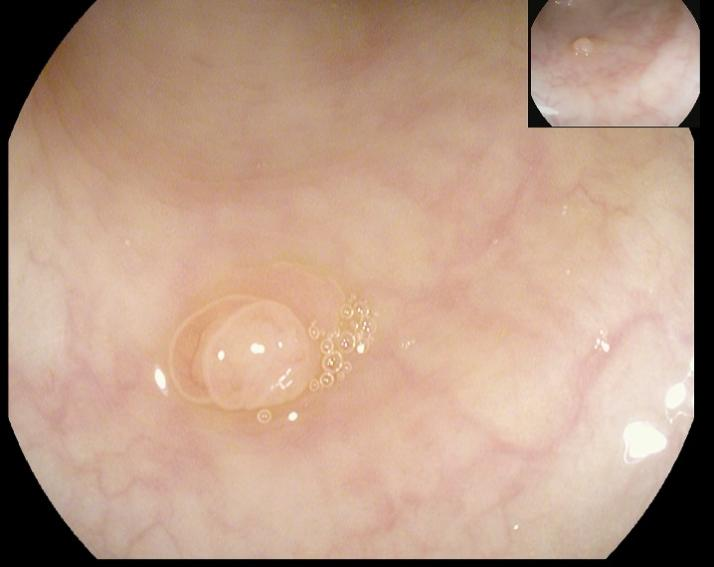

陈先生(44岁,乙状结肠息肉,图2)

肠镜一照,息肉现形!形态各异的大肠息肉,离癌有多远?(图2)

图2

病理诊断:(乙状结肠)管状腺瘤,局灶癌变-黏膜内癌(腺癌),脉管未见癌栓,蒂未见累及。

解读:这是从腺瘤发展成癌的典型案例。“局灶癌变”指息肉中只有一小部分区域发生了真正的癌变。“黏膜内癌”指癌细胞仍局限于黏膜层内,尚未穿透黏膜肌层向更深层浸润。脉管无癌栓、蒂部未累及是非常积极的信号,表明癌细胞尚未通过血管/淋巴管扩散,也未侵犯息肉蒂部。此时完整切除息肉,很大可能达到根治效果。距离进展期癌:非常近,但尚属极早期,原位癌/粘膜内癌。